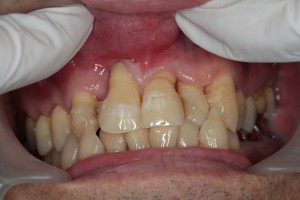

歯の周りの汚れや歯石を除去して、きれいになると歯ぐきの炎症が治まってきます。

しかし、歯周病の進行した歯は支えてくれる骨が少ないため、そのままでは噛むたびに揺れて痛んだり、負担に絶えられず、再び炎症を起こしてきてしまいます。

そのため、しっかり歯が機能するように全体の噛み合わせの調整を行ったり、つながったかぶせものを入れて、歯と歯を固定して揺れない状態をつくります。

歯周病の治療を行い、噛み合わせを整えて、最終的なかぶせものでつなげて歯を守っています。

健康的な引き締まったピンク色の歯ぐきになっています。